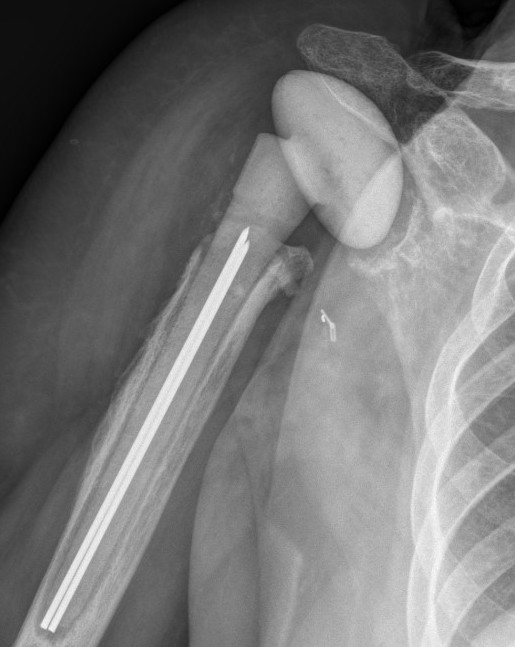

Hum shafthum shaftHum shaft

Stable humeral component treated with ORIF

hum #Hum #Hum #